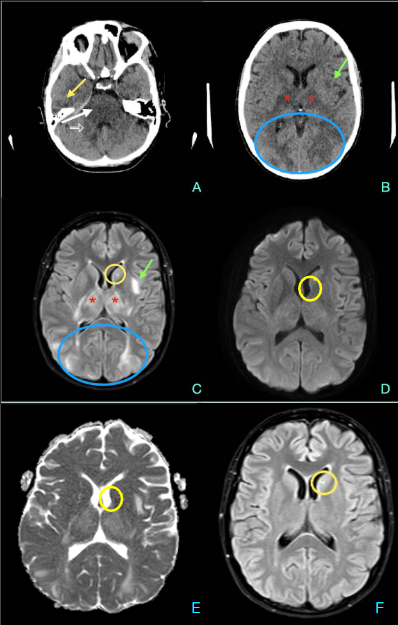

Resonancia magnética: secuencias ponderadas en T1 con gadolinio en plano axial (A), sagital (B) y coronal (C): Masa extraaxial de aspecto heterogéneo, bien definida, con un intenso realce periférico, de 42 x 41 x 38 mm (AP x TR x CC) en la línea media frontobasal. La lesión está en contacto con la lámina cribiforme y parece originarse del bulbo y tracto olfatorio izquierdo. Aisladas formaciones quísticas periféricas. Secuencia ponderada en T2 plano coronal (D): extensa área de hiperseñal T2 que se extiende por la sustancia blanca del lóbulo frontal izquierdo.

La RM es la técnica de elección para su diagnóstico, mostrando una masa extraaxial bien delimitada, de intensidad baja o intermedia en imágenes ponderadas en T1 e hiperintensas en T2. La hiperintensidad en T2 puede ser homogénea o mostrar un aspecto “en diana” con alta intensidad en la periferia de la lesión.